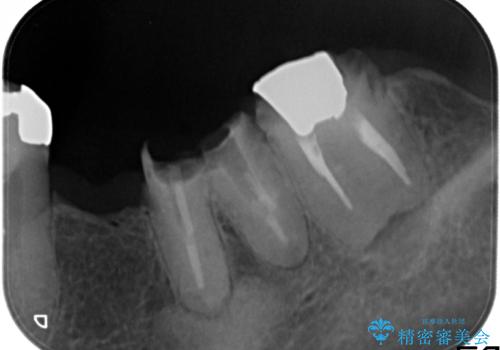

奥歯2本は虫歯により残っている健全歯質が少ないため、保存が難しい状態でした。

虫歯を丁寧に除去した後に歯根を分割し、骨を削合して健全歯質を露出させる骨外科手術を行いました。

手術後に根管治療を行い、歯肉と骨の治癒を十分に待った後ブリッジによる補綴治療を行いました。